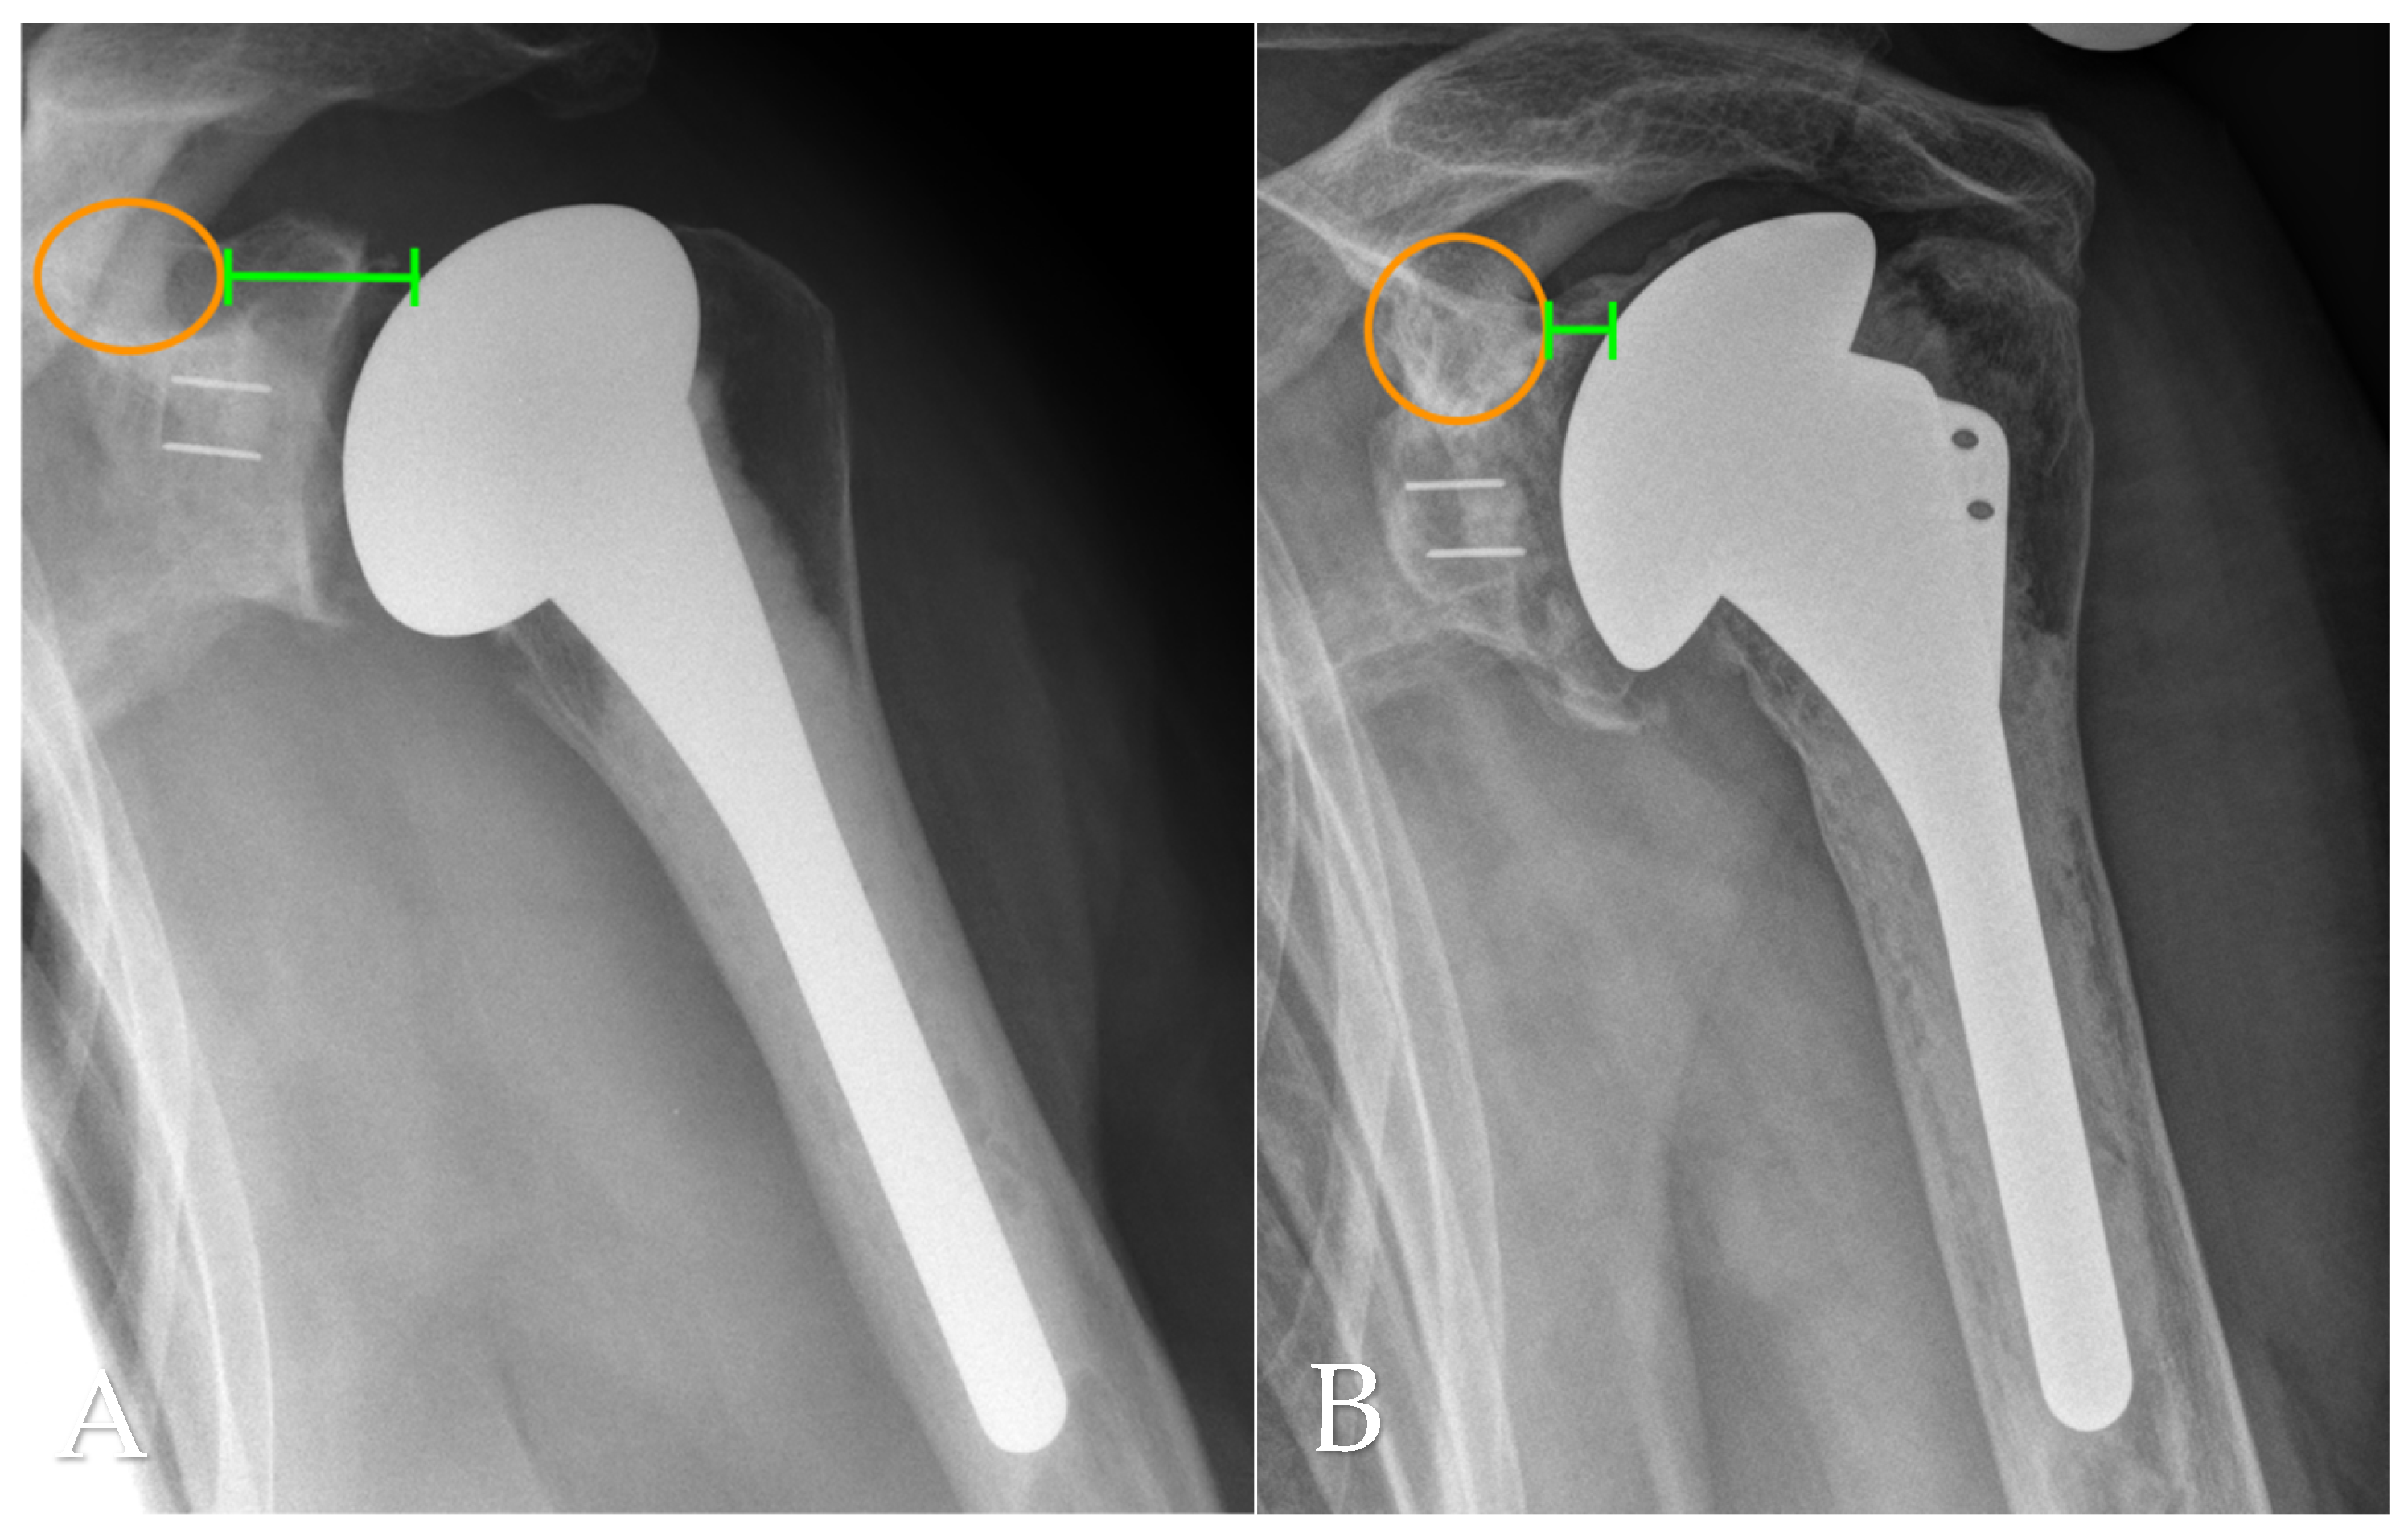

Radiographic evaluation at final follow-up was based on standardized anteroposterior and scapular Y-view radiographs, which were also consistently obtained during routine follow-up assessments. Postoperative imaging was used to analyze several anatomical and implant-related parameters, including the critical shoulder angle (CSA) as per Moor et al. [11], the acromiohumeral distance (AHD), lateral offset (LO), the head–stem index (HSI), and the extent of glenoid erosion following the classification systems proposed by Sirveaux [12], Lévigne, and Franceschi [13]. AHD was determined by measuring the vertical distance between the lateral aspect of the acromion’s undersurface and a horizontal line aligned with the upper border of the greater tuberosity, in accordance with the method described by Berthold et al. [14] (see Figure 1B). The CSA was calculated using lines drawn from the superior to inferior margins of the glenoid and from the inferior glenoid pole to the lateralmost point of the acromion, following Moor’s protocol [11] (Figure 2A). Lateral offset was assessed on true AP views by calculating the horizontal distance from the humeral head center to a vertical reference line extending from the lateral acromion margin to the humeral shaft (Figure 1A). The head–stem index (HSI) was computed as the ratio between the diameter of the humeral head and the shaft (stem) diameter, as outlined by Hochberger et al. [15] (Figure 2B). Assessment of glenoid erosion was conducted on AP radiographs and classified according to the established schemes of Sirveaux, Lévigne, and Franceschi, which consider both the magnitude of bone loss and the degree of medial displacement of the joint line relative to the scapular anatomy.

Figure 2. (A) Critical shoulder angle (CSA; yellow line) and (B) humeral head-stem-index (HSI; yellow circles) measured on an anteroposterior radiograph at final follow-up.